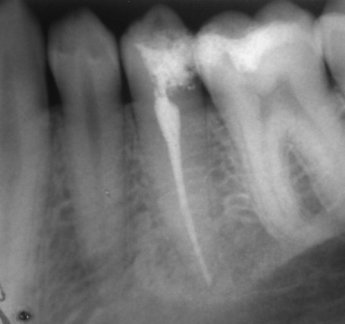

Добре пролекувани зъби

Ендодонтия